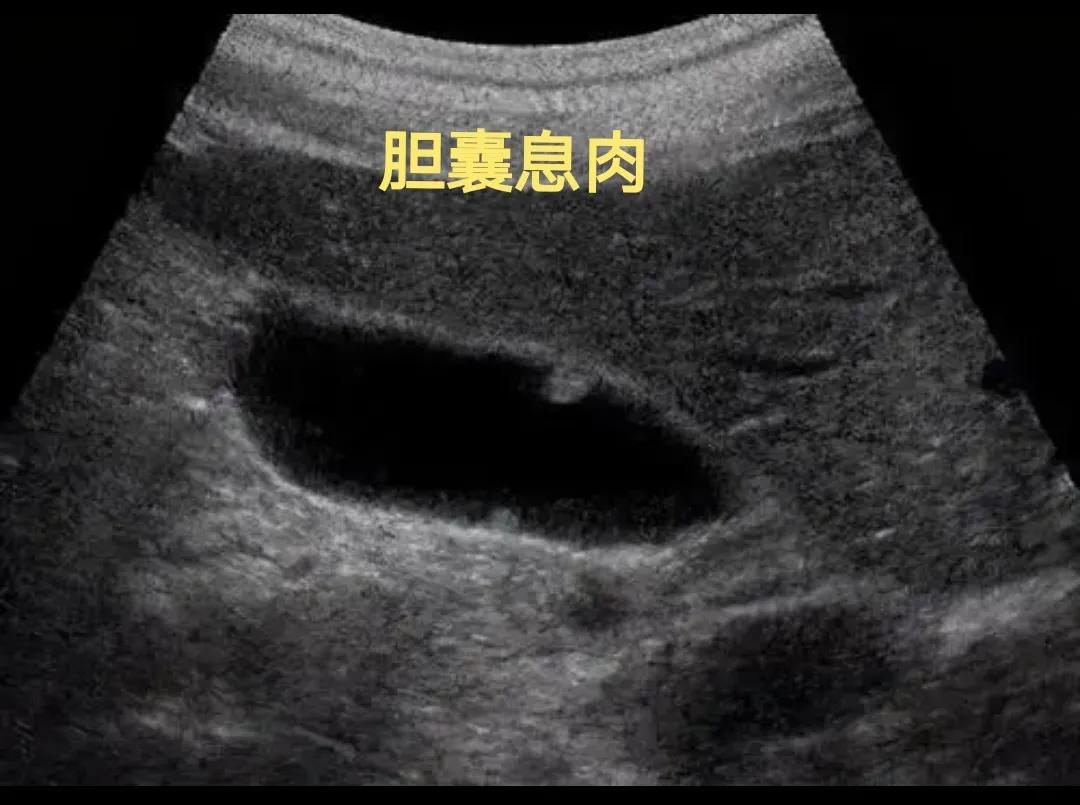

胆囊息肉

胆囊息肉是指起始于胆囊壁、向胆囊腔内突出或隆起的病变。 胆囊息肉又叫做“胆囊息肉样病变” ,因为这种疾病只有在做胆囊超声检查时才能发现,一般没有临床症状,术前知道具体是什么疾病,更不能确定良性还是恶性疾病的定性,只有做了手术以后才能得知。

胆囊息肉分为假性息肉和真性息肉。其中,假性息肉包括炎性息肉、腺肌增生、胆囊腺肌病、胆固醇息肉等。真性息肉包括腺瘤性息肉和息肉型胆囊腺癌,也包括脂肪瘤、血管瘤、平滑肌瘤和神经纤维瘤。

在胆囊息肉疾病中,胆固醇息肉最常见,但是发生恶变的几率非常低,而胆囊腺瘤发生癌变几率在30%左右,需要特别注意。

对于胆囊息肉直径>1cm,息肉基底宽、单发、合并胆囊结石并且年龄大于50岁的人来说,这些人是建议做胆囊切除手术的,以防止癌变。

对于直径<1cm,年龄比较小的患者来说,虽然不需要立即做手术,也是需要定期复查的,如果息肉不增长,那就定期随访可以了,如果息肉明显增长的话,也是需要及时手术的。